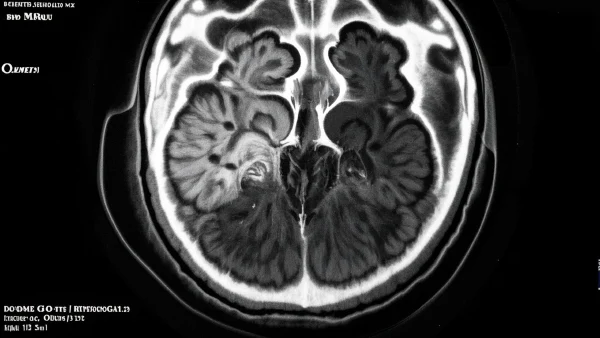

04 听神经瘤在影像下长什么样?

在影像学界,一位50岁的男士因右耳逐渐严重的听力障碍被送来做检查,MRI发现其在桥小脑角区有一个类圆形、边界清楚的肿瘤,最大径约2.5厘米,就是典型的听神经瘤表现。

听神经瘤的典型影像学特征主要包括:

- 1. 形状:绝大多数为椭圆或圆形肿块,边界光滑,大小不等。有点像一颗慢慢膨胀的葡萄。

- 2. 位置:多位于“桥小脑角区”,即内耳和脑部交界的区域。

- 3. 增强特征:注射显影剂后,肿瘤会明显“亮起来”(增强),但中心区偶见不均匀(因肿瘤内部发生轻微囊变)。

- 4. 与周围结构的关系:大肿瘤可以压迫周围听神经、面神经甚至小脑,引发复杂症状。